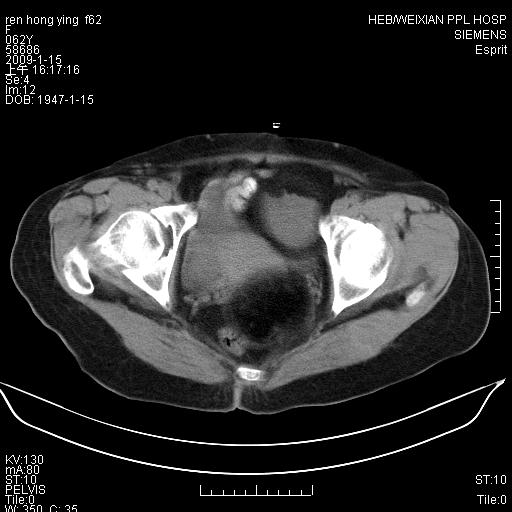

标题: CT17892:盆腔肿块

患者,女,61岁,无自觉症状,体检时发现盆腔肿块。

盆腔内多发性畸胎瘤。

典型畸胎瘤(皮样囊肿)